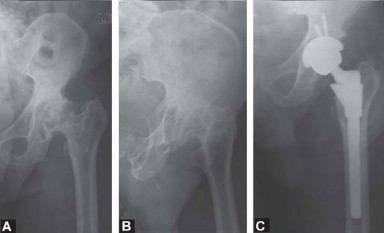

Uncemented Acetabular Revision with Hemispherical Cup INDICATIONS AND CONTRAINDICATIONS A hemispherical cemen…